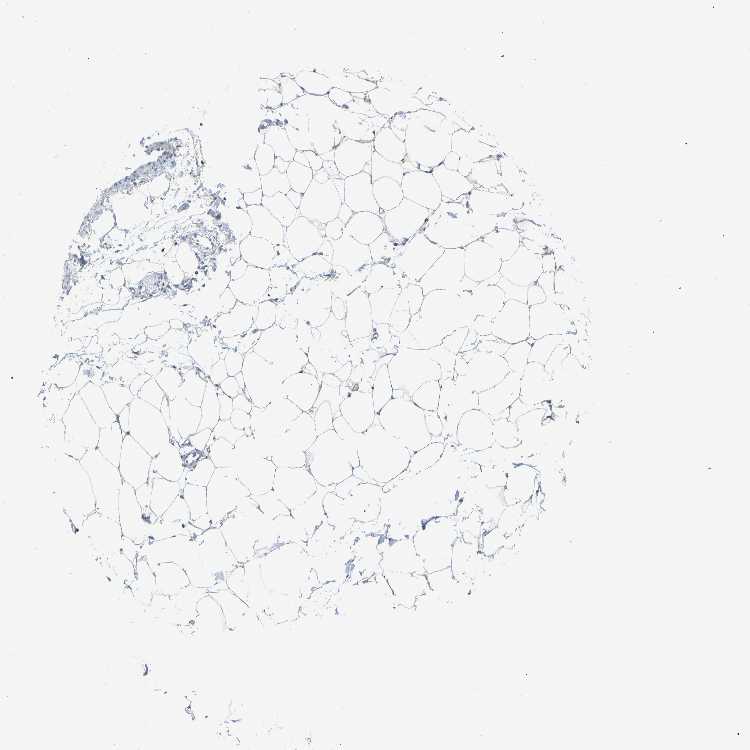

SOFT TISSUE 1 - Antibody stainingi

Antibody staining in the annotated cell types in the current human tissue is reported as not detected, low, medium, or high, based on conventional immunohistochemistry profiling in selected tissues. This score is based on the combination of the staining intensity and fraction of stained cells.

Each image is clickable and will lead to virtual microscopy that enables deeper exploration of all samples and also displays staining intensity scores, fraction scores and subcellular localization as well as patient and tissue information for each sample.

Antibody HPA016552

Fibroblasts Low

Peripheral nerve Not detected